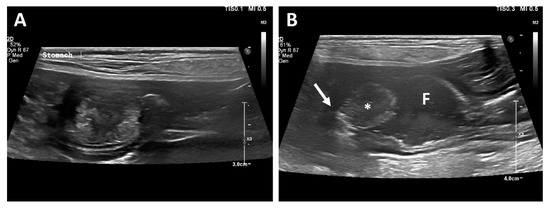

Computed tomography (CT; LightSpeed, GE Medical Systems, Milwaukee, WI, USA) was performed to evaluate the gastric lesion. With the patient positioned in ventral recumbency, a contrast study was performed after administration of the contrast medium (Omnipaque 300, GE Healthcare, Milwaukee, WI, USA). Contrast uptake was assessed in the late venous phase. Post-contrast CT images revealed a mass (17 × 12 × 15 mm) cranial to the pyloric antrum, and the contrast enhancement of the mass was similar to that of the surrounding gastric wall (Figure 2). No contrast leakage was identified.

Figure 2. Post-contrast transverse (A) and dorsal (B) CT images of the abdomen. A wide-based, polypoid mass (arrowhead) with heterogeneous contrast enhancement.